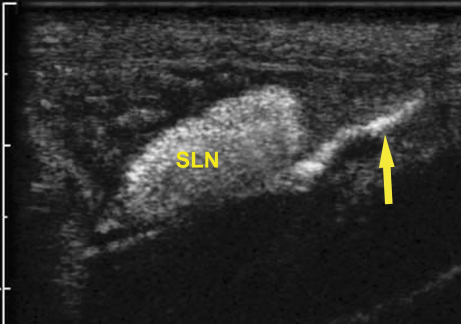

在访问期间,我的学习重点集中在了该研究所基础研究和动物实验方面,参观了多项基础研究的进行,并通过了该大学的动物实验考试,获取了参与动物实验的宝贵机会:光声成像超高频超声的应用——肝原位癌造影联合放疗(裸大鼠)、光声成像超高频超声的应用——皮下乳腺癌携氧微泡造影放疗增敏(裸小鼠)、腹主动脉亚谐波测压(兔)、低频超声在骨折愈合中的作用(兔)、黑色素瘤淋巴结转移超声造影(猪)、亚谐波联合微球体定量评估卵巢血流灌注预实验(狗)。此外,刘吉斌教授还开设小讨论课程,为我们介绍费城地理、生活、风土人情,并对杰弗逊大学医学院的背景、现状进行了深入浅出的讲解。在每次实验开始前详细介绍整个实验流程及设计理念,特别是实验向临床转化的过程;来自祖国各地的访问学者也都纷纷对自己的研究领域及医院科室文化进行相应的介绍,令我受益匪浅。